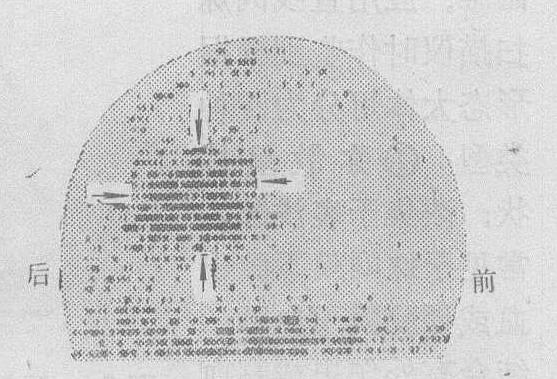

❷203Hg新醇能很快从血液中清除,在注射后5小时,血液中浓度降至10%以下,对头皮、肌肉和骨骼影响较小,因此扫描结果比较满意(图1ab),适宜于诊断颅后窝肿瘤,但易浓集于肾小管内,照射量大,故已逐渐少用。

图1a 前后位,左额星形细胞瘤203Hg新醇700mCi

图1b 左侧位,同上